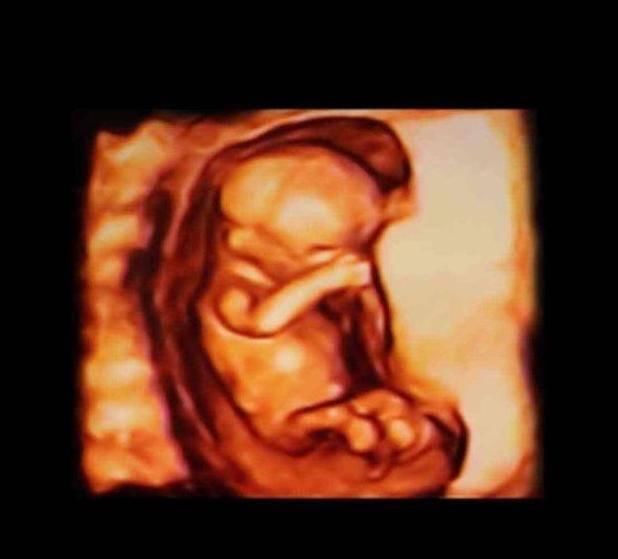

13-15周,胎儿的眼睛开始转动,大脑也在飞速地发育,胎儿的小脸已经和成人差不多了,神经元开始增多,条件反射也开始增加,胎儿身材比例越来越合理了。